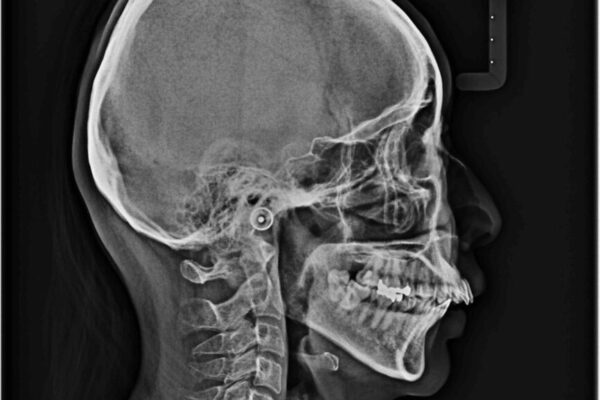

治療前

• 上顎前歯の突出を軽減 インビザラインによる抜歯矯正 治療前画像